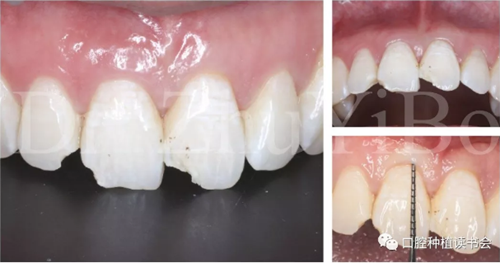

臨床檢查發(fā)現(xiàn):右上中切牙冠根折,斷面位于齦緣下4到5個毫米。左上中切牙及右上側切牙,切角缺損,牙髓活力正常(圖7)。

術前cbct顯示:右上中切牙牙根牙槽突類型為一型(圖8)。牙齦為厚型牙齦類型;咬合關系基本正常。

圖7 外傷導致11冠根折

圖8 CBCT:11可見明顯根折線,無法保留